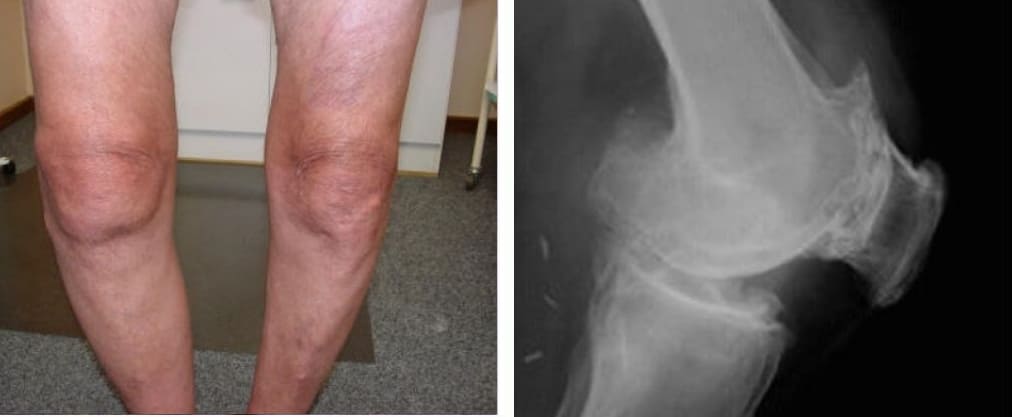

Atrofia e forte deformação das articulações dos joelhos, dor constante e aguda mesmo com o mínimo movimento.

Atrofia da cartilagem do joelho, necrose dos tecidos, destruição total da articulação e amputação inevitável.